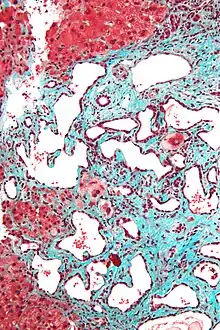

Low magnification micrograph of a bile duct hamartoma. Trichrome stain.